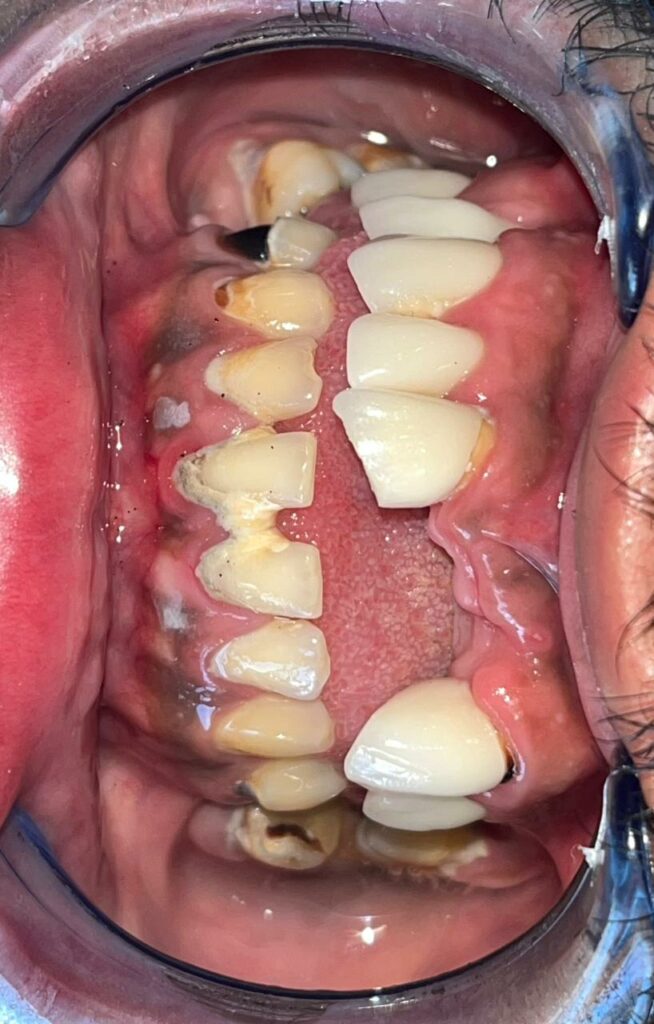

Le remodelage du sourire est un ensemble de techniques esthétiques et fonctionnelles permettant de transformer ou d’harmoniser le sourire.

Il peut associer plusieurs soins tels que :

Chaque plan de traitement est unique, conçu à partir d’une étude précise du visage et des attentes du patient.